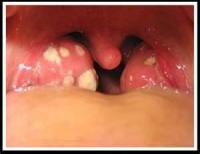

有些咳嗽病人,檢查時在胸部可聽到咻咻的喘鳴聲,尤其用力吸氣後、再用力吐氣就會出現。有喘鳴聲代表氣管水腫、肌肉層收縮及分泌物增多,空氣呼出去時,像是通過窄巷或門縫,就發出尖銳的咻咻聲。這樣的病人,外表不見得有不舒服或呼吸困難,不過一定是支氣管有發炎變化才會如此,咳嗽就是反映這些發炎的生理現象。有喘鳴不一定代表有氣喘病,但正常小孩是不該有那麼多次喘鳴現象。

氣喘病的變化是在支氣管,而不在肺部。這些變化是可逆性的,但如不小心徹底治療,久而久之也可能形成支氣管的纖維化,使肺功能退化。病兒之病變,有可能只是特發於兩歲內幼兒的毛細支氣管炎,也有可能是一些病毒感染造成的支氣管炎,一過了五、六歲就不再出現;但也很可能是因過敏體質導致的支氣管性氣喘,或許還會終身隨時發作。如果咳嗽帶喘鳴有三、四次以上,本身又常流鼻水不易痊癒,或曾被診斷皮膚有濕疹,家長也有過敏病史,則氣喘病的可能性非常大。

5、 急性咽炎或咽扁桃腺炎:發燒約三至五天,多數是病毒性,如為A族鏈球菌引起的,用抗生素可縮短發燒時間,有些會併發猩紅熱或風濕性心臟病。

A族溶血型鏈球菌之所以可怕在於其感染後如果沒有經過完整的抗生素治療,經過一段時間後會對腎臟和心臟造成破壞。風濕熱是由於罹患A型鏈球菌咽喉炎一至五週後所引發的全身性免疫發炎反應,包括心臟、關節、腦部及皮膚等器官,其中以心臟的侵犯最為重要。A型鏈球菌咽喉炎感染後約有百分之三的機會造成風濕熱,因此當兒童喉嚨痛,喉嚨發炎時,家長不可掉以輕心。